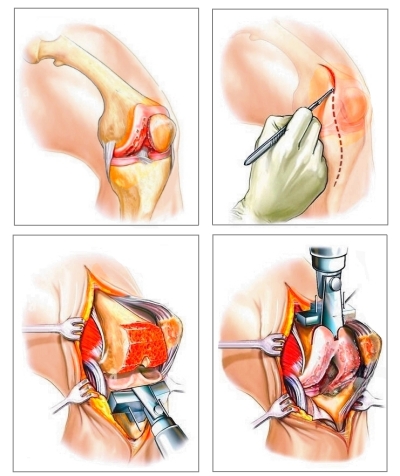

Vietoj galimų 100 metų (mūsų sąnariai turi tokį potencialą), žmonės kenčia nuo degeneracinių ligų jau po 50, o vis dažniau — jau po 40 metų! Žmonės nesupranta ligos rimtumo ir kreipiasi pagalbos, kai jau per vėlu, ir chirurginė operacija — vienintelė, ką medicina gali pasiūlyti.

ENDOPROTEZAVIMAS (sąnario pakeitimas dirbtiniu) —

tai labai sudėtinga ir rizikinga operacija, kuri

dažnai sukelia įvairių komplikacijų, iki pat

savarankiškumo praradimo ir negalios.

ENDOPROTEZAVIMAS (sąnario pakeitimas dirbtiniu) —

tai labai sudėtinga ir rizikinga operacija, kuri

dažnai sukelia įvairių komplikacijų, iki pat

savarankiškumo praradimo ir negalios.

Jei laiku nesiimsite priemonių, tai baigiasi visišku sąnario praradimu. Ir vienintelė išeitis, kuri lieka — tai operacija sąnariui pakeisti dirbtiniu. Bet aš PRIMYGTINAI PRAŠAU iki to neprivesti. Sąnario keitimas ir pati chirurginė intervencija dažnai baigiasi infekcija, iki pat galūnės amputacijos!